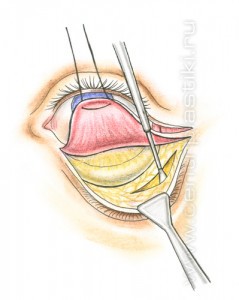

Рис. 6 Мышцу, аккуратно приподнимают и отделяют до края глазницы. Рис.7. Жировые «грыжи» опускаются вниз за край глазницы и фиксируются к надкостнице несколькими нитями, Рис. 8-9 таким образом, удается заполнить слезную и веко-щечную борозды Рис. 10.

Рис. 7

Рис. 8